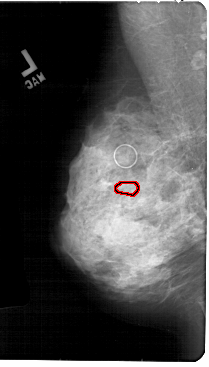

A_1852_1.LEFT_MLO

LEFT_MLO LINES 5491 PIXELS_PER_LINE 3121 BITS_PER_PIXEL 12 RESOLUTION 43.5 OVERLAY

FILE: A_1852_1.LEFT_MLO.OVERLAY

TOTAL_ABNORMALITIES 1

ABNORMALITY 1

LESION_TYPE CALCIFICATION TYPE PUNCTATE DISTRIBUTION CLUSTERED

ASSESSMENT 4

SUBTLETY 2

PATHOLOGY MALIGNANT

TOTAL_OUTLINES 1

BOUNDARY